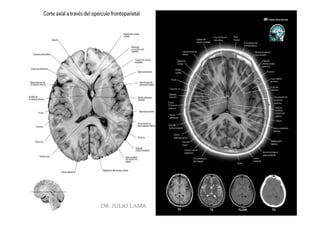

DR. JULIO LAMA

Pregrado – Dr Yee